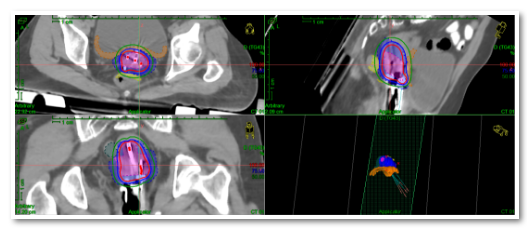

天津医科大学肿瘤医院放射治疗科在院领导和科室主任推动下,积极开展影像引导下的肿瘤个体化三维插植近距离放疗。3月12日,中国抗癌协会近距离放疗专委会常委、天津市医学会妇科肿瘤学分会常委、天津医科大学肿瘤医院放射治疗科副主任医师陈杰团队在近距离治疗室、物理室、CT定位室的密切配合下,针对两名宫颈癌外照射后宫旁肿瘤消退不明显的患者,进行了CT引导下的三维插植后装放疗,成功完成了天津市首例难治性宫颈癌CT引导下三维立体插植近距离放疗

在完成前期准备后,陈杰主任团队将插植针置入患者宫腔,通过放疗专用CT、MR扫描确认并调整插植针的位置,利用三维后装放疗计划系统进行靶区和正常器官的勾画,快速制定放疗计划,精准实施近距离放疗,顺利完成治疗。

影像引导下的三维插植近距离治疗,可以通过三维视角来进行施源器的置入与固定,定位更精确。根据不同靶区,可以采用徒手插植、模板插植、徒手结合模板插植等个体化植入施源器,可以准确地定位肿瘤组织的位置,通过非共面多角度进针,使肿瘤放疗靶体积达到处方剂量要求,在给予高剂量照射的同时,保证肿瘤周围正常组织受到照射的剂量控制在可接受范围内,从而提高患者的治疗效果和安全性,为晚期难治性的妇科肿瘤患者提供了新的治疗希望。